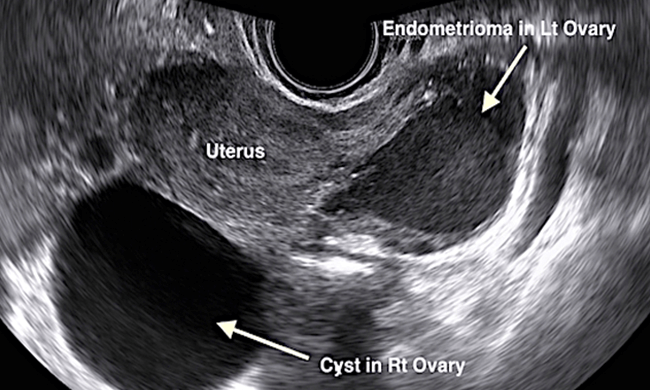

“血性囊肿”或子宫内膜异位症(或巧克力囊肿)是由子宫内膜异位症形成的。子宫内膜异位症是指子宫内膜长在子宫外,导致月经从子宫外流出。子宫内膜异位症会在卵巢内形成血性囊肿,导致痛经和盆腔疼痛。